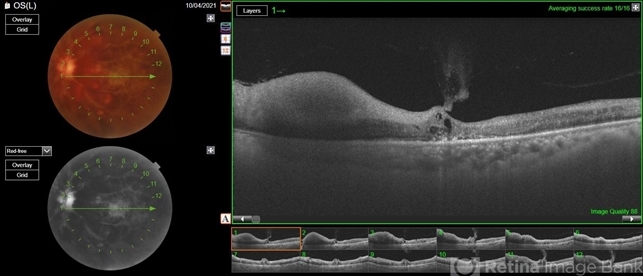

- optical coherence tomography (OCT), fundus photograph

- Nanda Lessi Hafni Eka Putri, MD (Ophthalmologist) & Ryan Mishbahuddin (Nurse), Ciawi General Hospital (Rumah Sakit Umum Daerah Ciawi)

Optical coherence tomography system

DRI OCT Triton Plus (Topcon) - Description

- Swept source OCT angiography of a 58-year-old man with hemorrhage in his left eye.